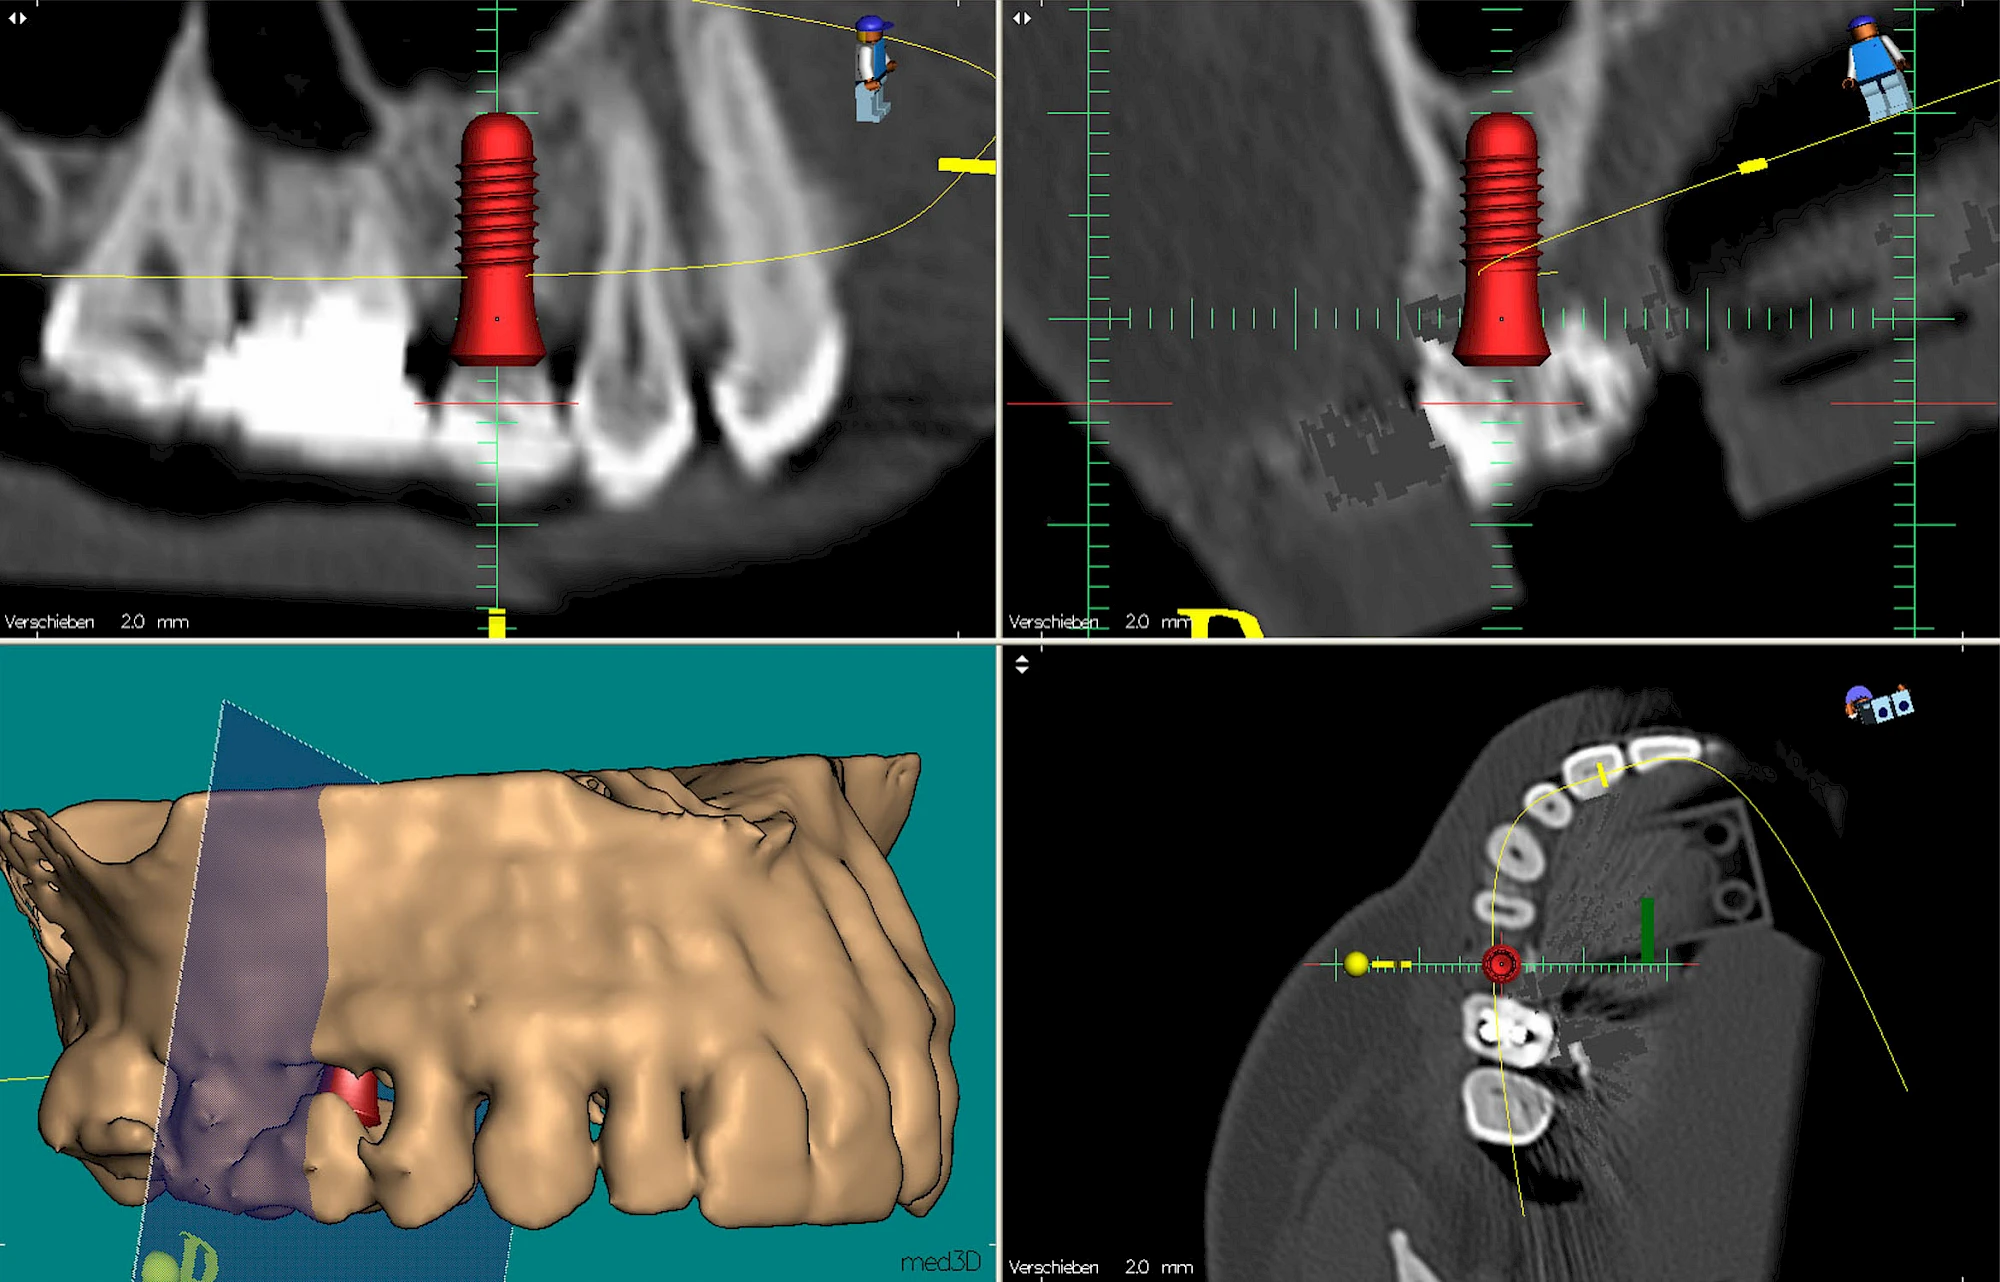

Damit Implantate an der richtigen Stelle im Kieferknochen platziert werden könen, gibt es heute vielfältige Möglichkeiten der Planung. In vielen Situationen kann die Erfahrung des Zahnarztes ausreichend sein.

Nicht selten ist jedoch auch eine technisch aufwändigere Vermessung im Vorfeld sinnvoll, z. B.:

- Wenn sich der Kieferknochen abgebaut hat

- Wenn der Nervverlauf im Unterkiefer beachtet werden muss

- Wenn die Ausdehung der Kieferhöhle im Oberkiefer beachtet werden muss

- Wenn wenige Restzähne keine gute Orientierung erlauben

In diesen Fällen kann die Planung mittels verschieden aufwendiger Röntgen-Techniken (Übersichtsaufnahme, DVT) ggf. unter Zuhilfenahme speziell angefertigter Planungsschablonen sinnvoll sein.